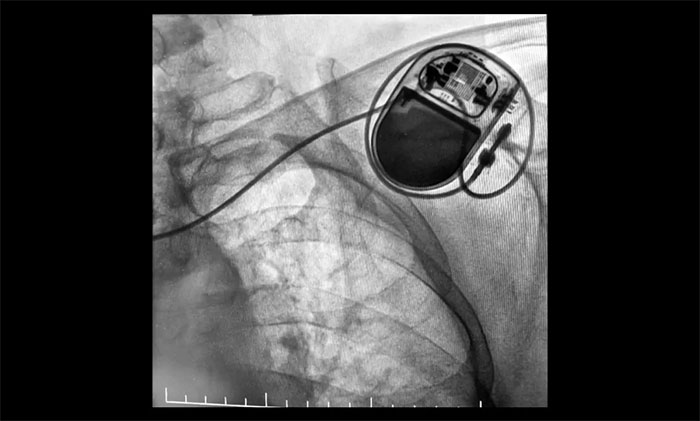

▲ 心臟起搏器順利植入

近日,上海藍十字腦科醫(yī)院成功完成首例永久性心臟起搏器植入手術(shù)。該患者為老年女性,因陣發(fā)性房顫伴顯著房性心律失常及竇房結(jié)功能不良,存在心跳驟停高風(fēng)險。手術(shù)在DSA引導(dǎo)下耗時40分鐘順利完成,出血不足5毫升,術(shù)后起搏器功能良好,患者正在康復(fù)中。